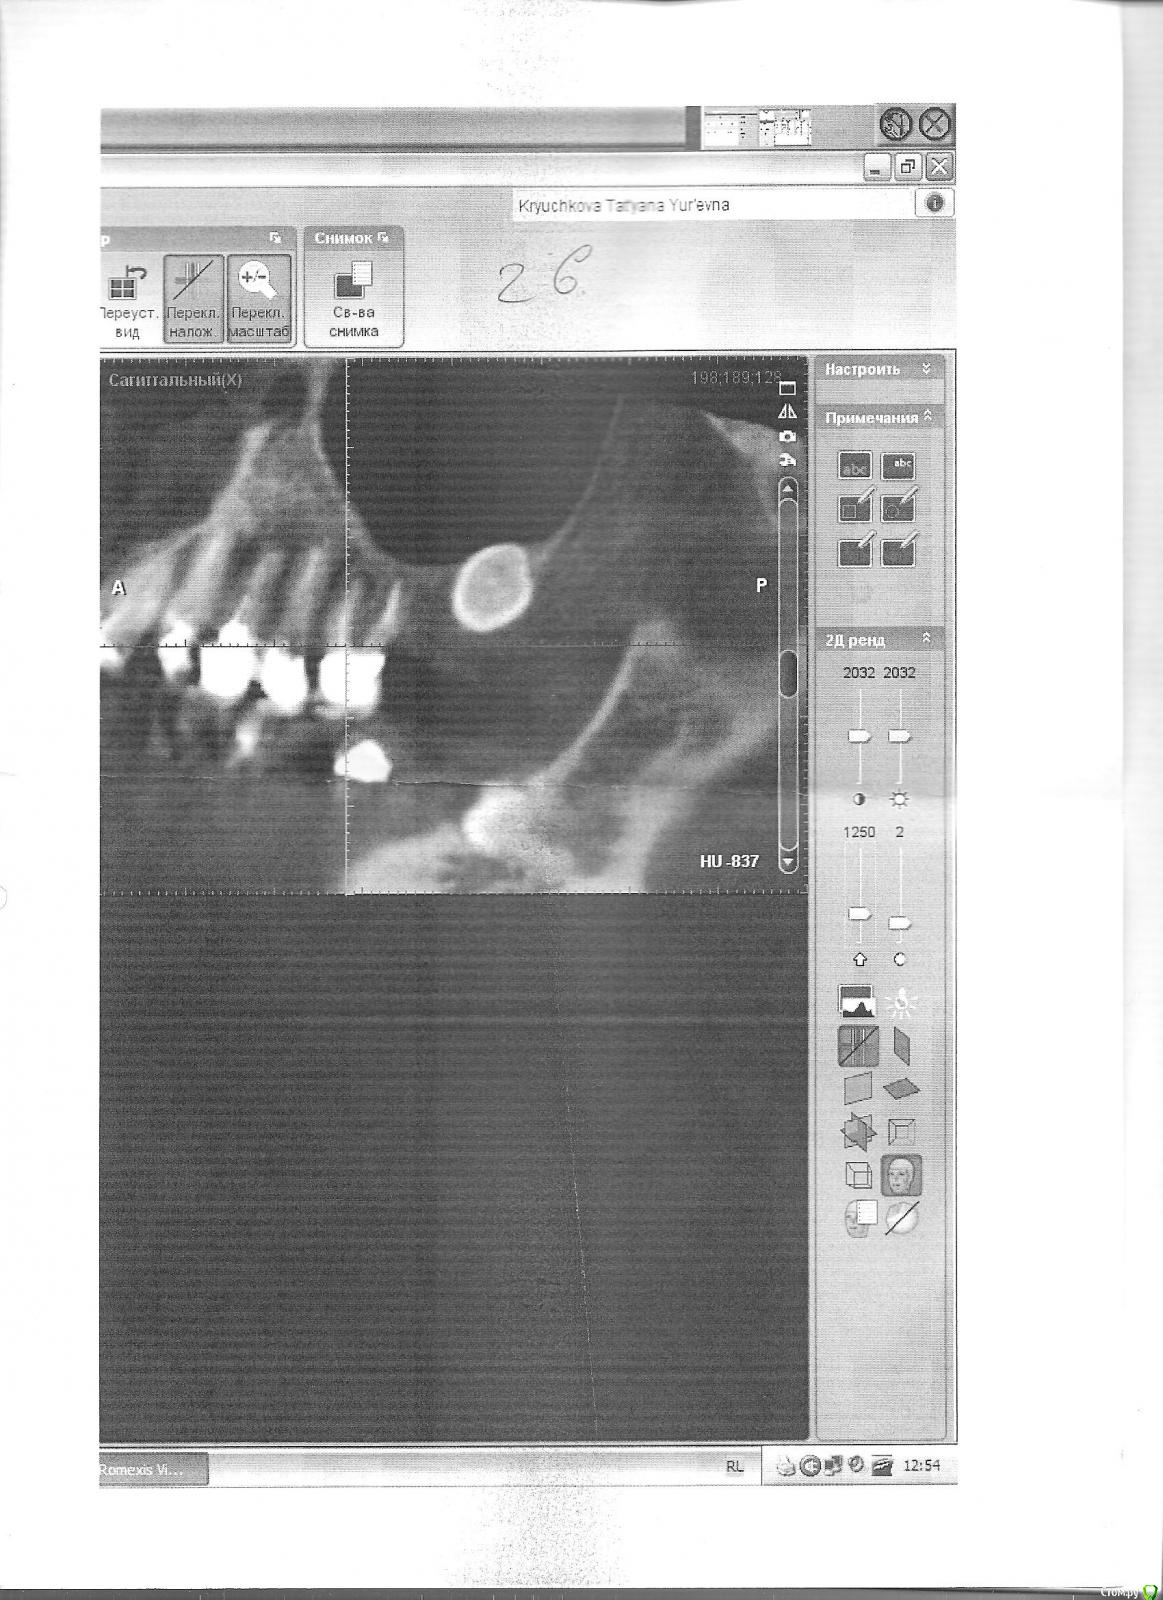

Возможно ли перелечить верхние шестерки? Срезы (если правильно называю) КТ прилагаются.

Проблемы вылезли на КТ, сделанном по другому поводу, эндо проверяли заодно, очередной прицельный снимок верхней левой (26?) врачу не слишком нравился. Сейчас, как мне сказали, на прицельном снимке  26 видно, что "мезиальный (так?) корень неспокоен" (пытаюсь цитировать). Прицельный снимок правой верхней шестерки (16?), сделанный после КТ, говорят, вообще воспаления не показывает. (Если эта информация была лишней, прошу прощения за многословие).